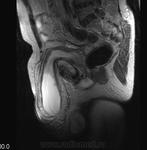

Так..., в виде иллюстрации предъявляю пахово-мошоночную грыжу

Вот прекрасный случай Игоря Ивановича!

Досмотр кишечника через 24 часа после приема пер ос "бария".

Классическая пахово-мошоночная грыжа.